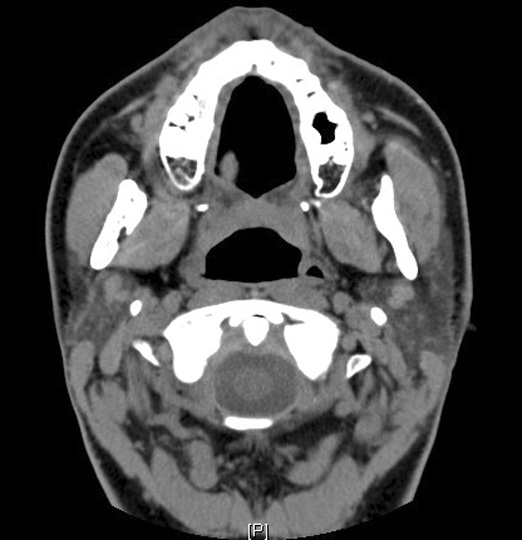

Identify the masseter muscles. Click the image for labeling.